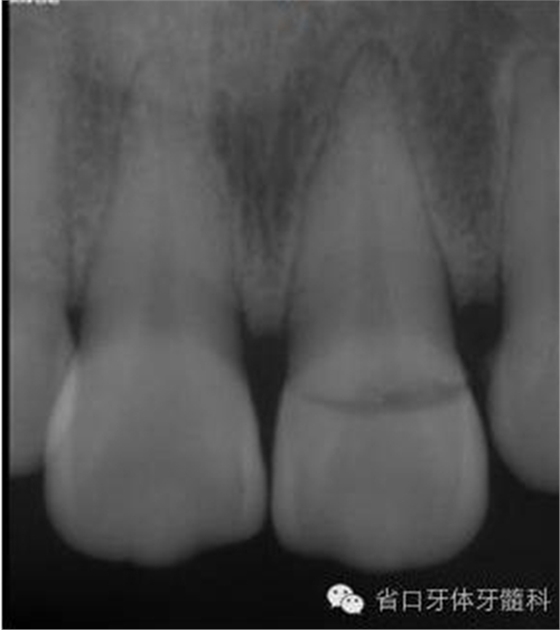

圖2. 術(shù)前口內(nèi)照片,21/冠折。

圖3. 術(shù)前X線片